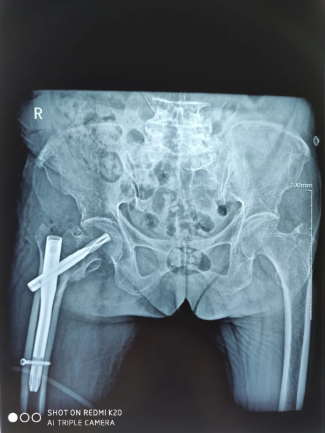

为了手术能顺利开展,张勇主任通过医务科邀请心血管内科、麻醉科、综合内科等多学科专家会诊,拟定“右股骨粗隆间粉碎性骨折闭合复位术PFNA内固定术”的手术方案,并制定了一套缜密的术前、术中、术后诊疗康复方案,完善术前准备。08月17日,在张勇主任的带领下,骨科团队为曾老太成功实施手术,整个术程一气呵成,既缩短手术时间,也减少术中出血,有效降低手术给患者带来的伤害。

术后X光